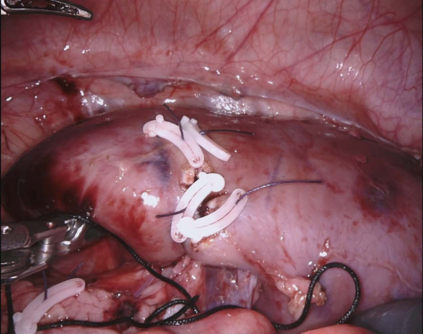

DeepSeek series have demonstrated outstanding performance in general scene understanding, question-answering (QA), and text generation tasks, owing to its efficient training paradigm and strong reasoning capabilities. In this study, we investigate the dialogue capabilities of the DeepSeek model in robotic surgery scenarios, focusing on tasks such as Single Phrase QA, Visual QA, and Detailed Description. The Single Phrase QA tasks further include sub-tasks such as surgical instrument recognition, action understanding, and spatial position analysis. We conduct extensive evaluations using publicly available datasets, including EndoVis18 and CholecT50, along with their corresponding dialogue data. Our comprehensive evaluation results indicate that, when provided with specific prompts, DeepSeek-V3 performs well in surgical instrument and tissue recognition tasks However, DeepSeek-V3 exhibits significant limitations in spatial position analysis and struggles to understand surgical actions accurately. Additionally, our findings reveal that, under general prompts, DeepSeek-V3 lacks the ability to effectively analyze global surgical concepts and fails to provide detailed insights into surgical scenarios. Based on our observations, we argue that the DeepSeek-V3 is not ready for vision-language tasks in surgical contexts without fine-tuning on surgery-specific datasets.